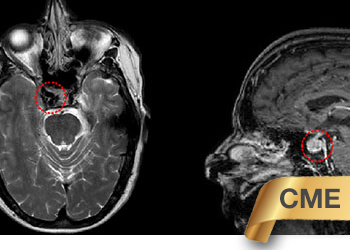

Endovascular:

CME:

Symptomatic Near-Occlusion of the Carotid Artery

Author: Jonathan L. Brisman M.D., F.A.C.S., Read More!